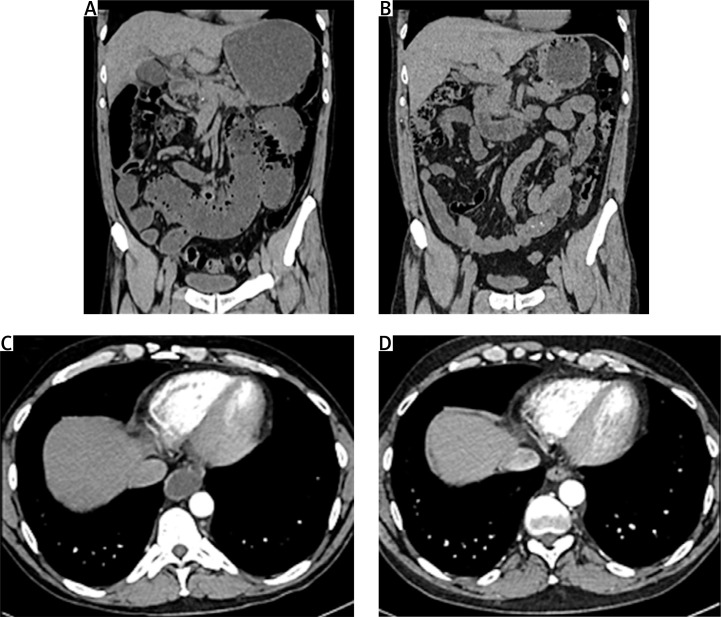

Chronic intestinal pseudo-obstruction (CIPO) is an infrequent and menacing complication of systemic sclerosis (SSc). While researchers report positive impact of rituximab (RTX) on CIPO in paraneoplastic syndrome, no case reports exist for SSc-associated CIPO. The aim of this case-based review is to analyses current literature in context of particular CIPO case description. This analysis was based on PubMed/MEDLINE database and was conducted using the selected key terms. Finally 40 studies/case reports and one case description from authors clinical experience were included into comparison and discussion. As conclusion description of successfuly treatment with RTX and intravenous immunoglobulins can confirm the suggestions from other studies that B-cells participate in the pathogenesis of SSc, making RTX a potentially effective therapeutic option also in coexisting CIPO.